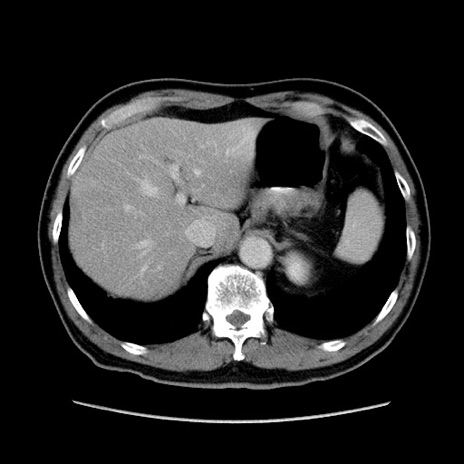

症例34(横断像)

【症例】60歳代 男性

【主訴】右鼠径部膨隆

【現病歴】1年程前より右鼠径部膨隆あり。自己にて還納可能だったため放置していた。3時間前より右鼠径部の脱出を認め、還納困難となり受診。

【身体所見】右鼠径部に小児頭大の膨隆あり。弾性硬であり、用手還納は困難。左鼠径部にも膨隆を認める。脱出はなし。